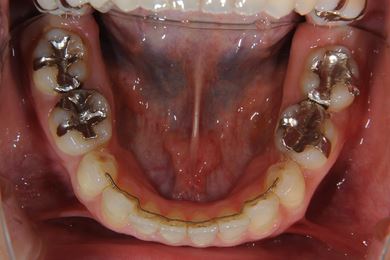

全顎矯正治療+セラミック治療

| 主訴 | 出っ歯 上顎前歯の並び | ||||||||||||||||||||||||||||||||

| 治療方針 | 上下歯牙がだいぶ前にでていて口が閉じづらい状態でした。なるべく金属が入っている歯を抜歯したいので、上下左右第二小臼歯を抜歯して、その隙間を利用して、口元をさげていきました。また、口元を最善の状態にうるために、抜歯スペースを使用したあと、上下左右のインプラントアンカー(釘)でより一層口元を後ろにさげていきました。ただの抜歯ケースよりだいぶ口元が下がっているのが分かります。抜歯したスペースががたつき(叢生量)で使用してしまう場合には、このような方法でより口元をさげることができます。お顔立ちがとてもよくなりました。とても協力していただけたので、しっかりと良くなることができました。 | ||||||||||||||||||||||||||||||||

| 治療内容 | 唇側矯正(ホワイト・上下左右第二小臼歯抜歯・上下インプラントアンカー)、オールセラミッククラウン1本(オールセラミック用土台1本)、ジルコニアフレームオールセラミッククラウン1本 | ||||||||||||||||||||||||||||||||